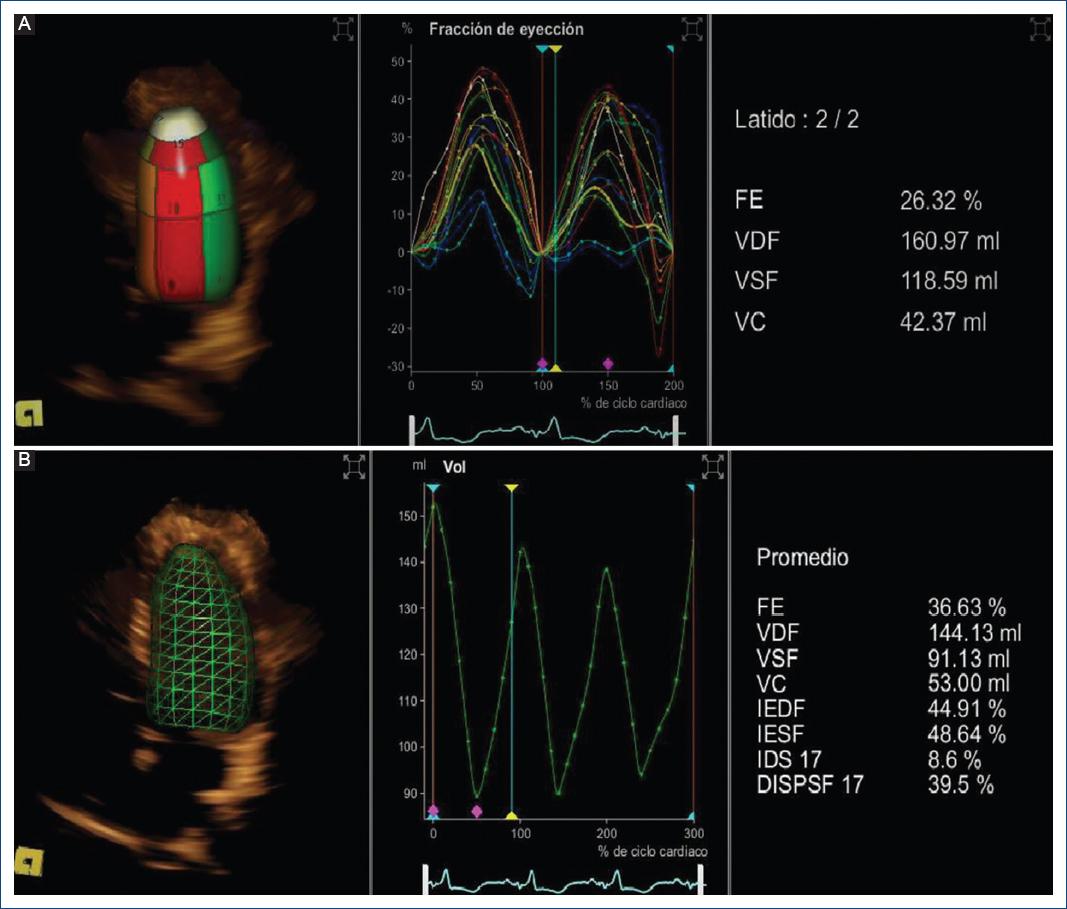

Posterior a 24 horas del procedimiento, se obtuvo ECG con reducción en la duración del QRS (Fig. 2). Se realizó una evaluación ecocardiográfica antes y después de la TRC mediante la técnica de rastreo de puntos (speckle tracking) sin estimulación se observó retraso en la conducción de las paredes anterior y posterior respecto a la pared septal, esto se explica por el BFA (Fig. 3). Posterior a la estimulación hubo mejoría significativa de la asincronía interventricular e intraventricular y la cuantificación de FEVI 3D final con software Syngo en Siemens Accuson S2000 fue del 36.6% (Fig. 4).

Figura 4 Cuantificación de la fracción de eyección ventricular izquierda (FEVI) 3D. A: la curva fracción de expulsión (FE)/tiempo es del 26.32%. B: posterior a la terapia de resincronización cardiaca y estimulación hisiana es del 36.6 % se observa una mejoría del 10.31 % de la FEVI. El volumen diastólico final (VDF) disminuyó de 160.97 mL (A) a 144.13 mL (B). El volumen sistólico final (VSF) disminuyó de 118.59 mL (A) a 91.13 mL (B). El volumen latido (VC) aumentó de 42.37 mL (A) a 53 mL (B). En el gráfico B, curva volumen/tiempo, se identificó mejoría en 10.63 mL en el volumen latido con respecto a la basal.